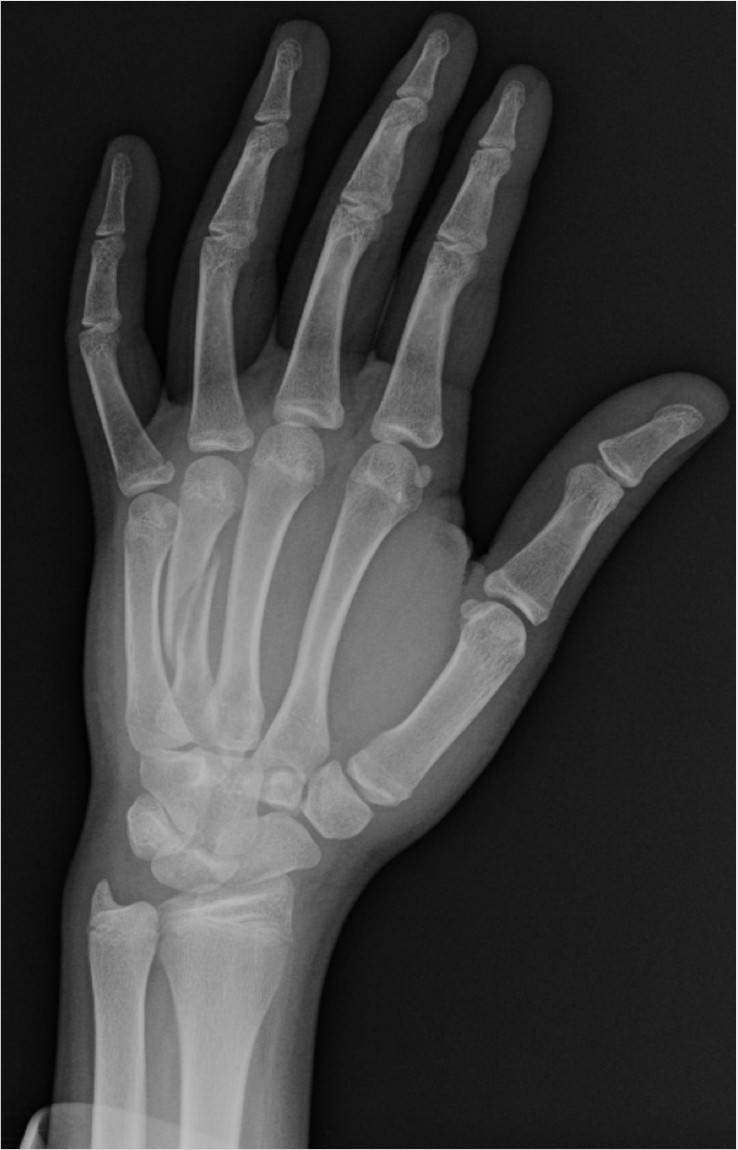

A 28-year-old left hand-dominant man presents with hand pain after striking someone with his left hand. The X-ray is shown above. On examination, overlapping of the patient′s ring and small fingers is noted while he makes a fist.

• Oblique extra-articular fracture of ring finger metacarpal shaft with angulation, rotation, and shortening,